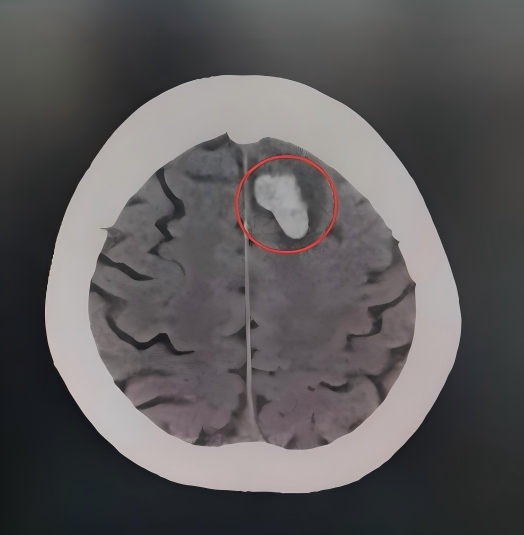

急诊团队迅速完成张大爷的心率、血压、血氧饱和度等关键指标监测。综合检查提示:老人左侧额叶脑挫裂伤,左侧股骨颈骨折,全身多处擦伤。

白色为创伤性颅内血肿,周边黑色为水肿

可以明显看到血肿和水肿范围在不断扩大

病情随时可能出现变化

张大爷的骨折和坏死需要尽快行手术恢复,但脑部的挫裂伤脑将在伤后48-72小时达到水肿高峰期,此时行手术,麻醉风险极高。另外考虑到张大爷的高血压已达到2级,过高的血压会加重颅内出血和脑水肿,过低的血压则可能会再次诱发脑梗。